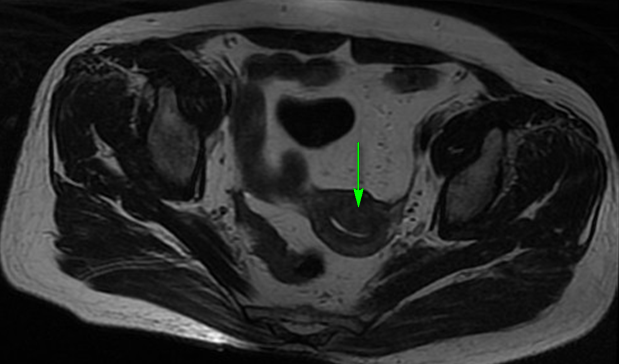

1、B超:内膜厚0.5cm,子宫多发肌瘤,较大者1.5*1.4cm,宫腔下段至宫颈管内见低回声,约1.9*1.9*2.8cm,请结合临床除外占位病变; 2、诊刮术,病理回报:低分化癌,符合透明细胞癌; 3、盆腔MRI:子宫内膜不规则增厚,结合带显示欠清,宫底部短T2结节影,肌瘤可能,宫颈饱满,后壁片状长T2信号。